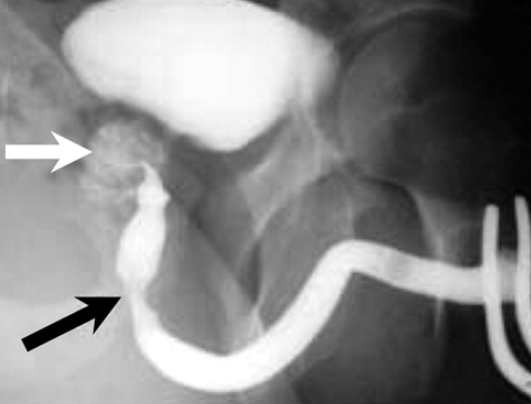

Godlman III